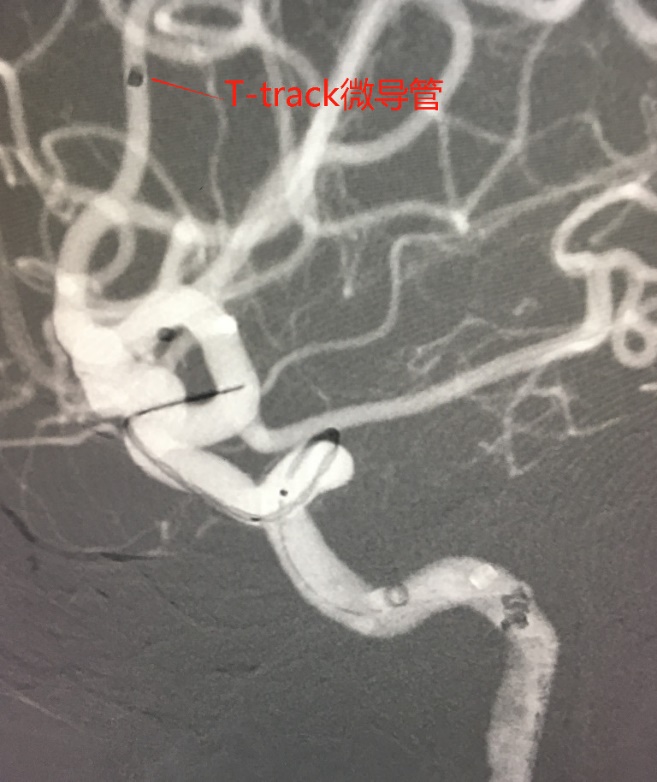

Tubridge®血管重建装置专用支架导管T-track到位,引入4.0mm*30mm支架。

准确定位后,锚定支架头端,缓慢推送支架的同时控制支架张力,顺利释放支架。

为进一步确保Tubridge®血管重建装置完美贴壁,上J型导丝支架内“按摩”。

多角度确认支架已完全贴壁。

- Tubridge®血管重建装置专用微导管T-track是0.029inch,相对来说,支撑力更强、更稳定。